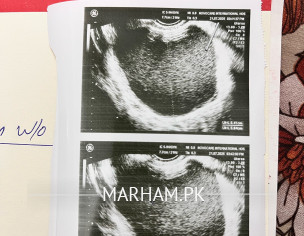

I want to ask what are the ideal procedures to remove chocolate cyst. It’s size is 7.7cm

Attach Photo here: